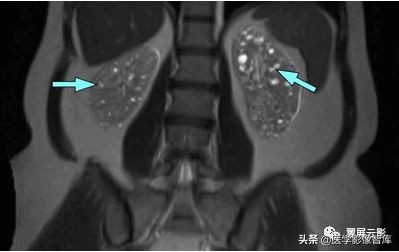

多囊肾

本病常合并多囊肝,此为先天性常染色体显性遗传性疾病,多数学者认为多囊肝是在多囊肾的基础上基因突变的结果,并定位于16号染色体上,也有学者认为该病是由于胚胎发育不良所导致,于胚胎早期管道形成时排列失常,造成无数迷管,于胚胎晚期未退化,且逐渐扩张成囊,成多发性囊肿病,根据发病年龄的不同,将其分为儿童型和成人型,本病多发生于双侧肾脏,可继发感染,结石以及囊内出血和囊壁钙化,也可以恶变,并有阻塞性黄疸及合并皮下囊肿的报道,临床上早期无症状,就诊时肾脏功能已经不同程度受损,肝功能受损程度较轻。

MRI表现为双肾增大和分叶状轮廓,多发囊肿多数为长T1长T2信号,出血性囊肿可为短T1长T2信号或长T1短T2信号,增强扫描所有病灶均不强化,应同时观察合并的多囊肝及胰脾多发囊肿。